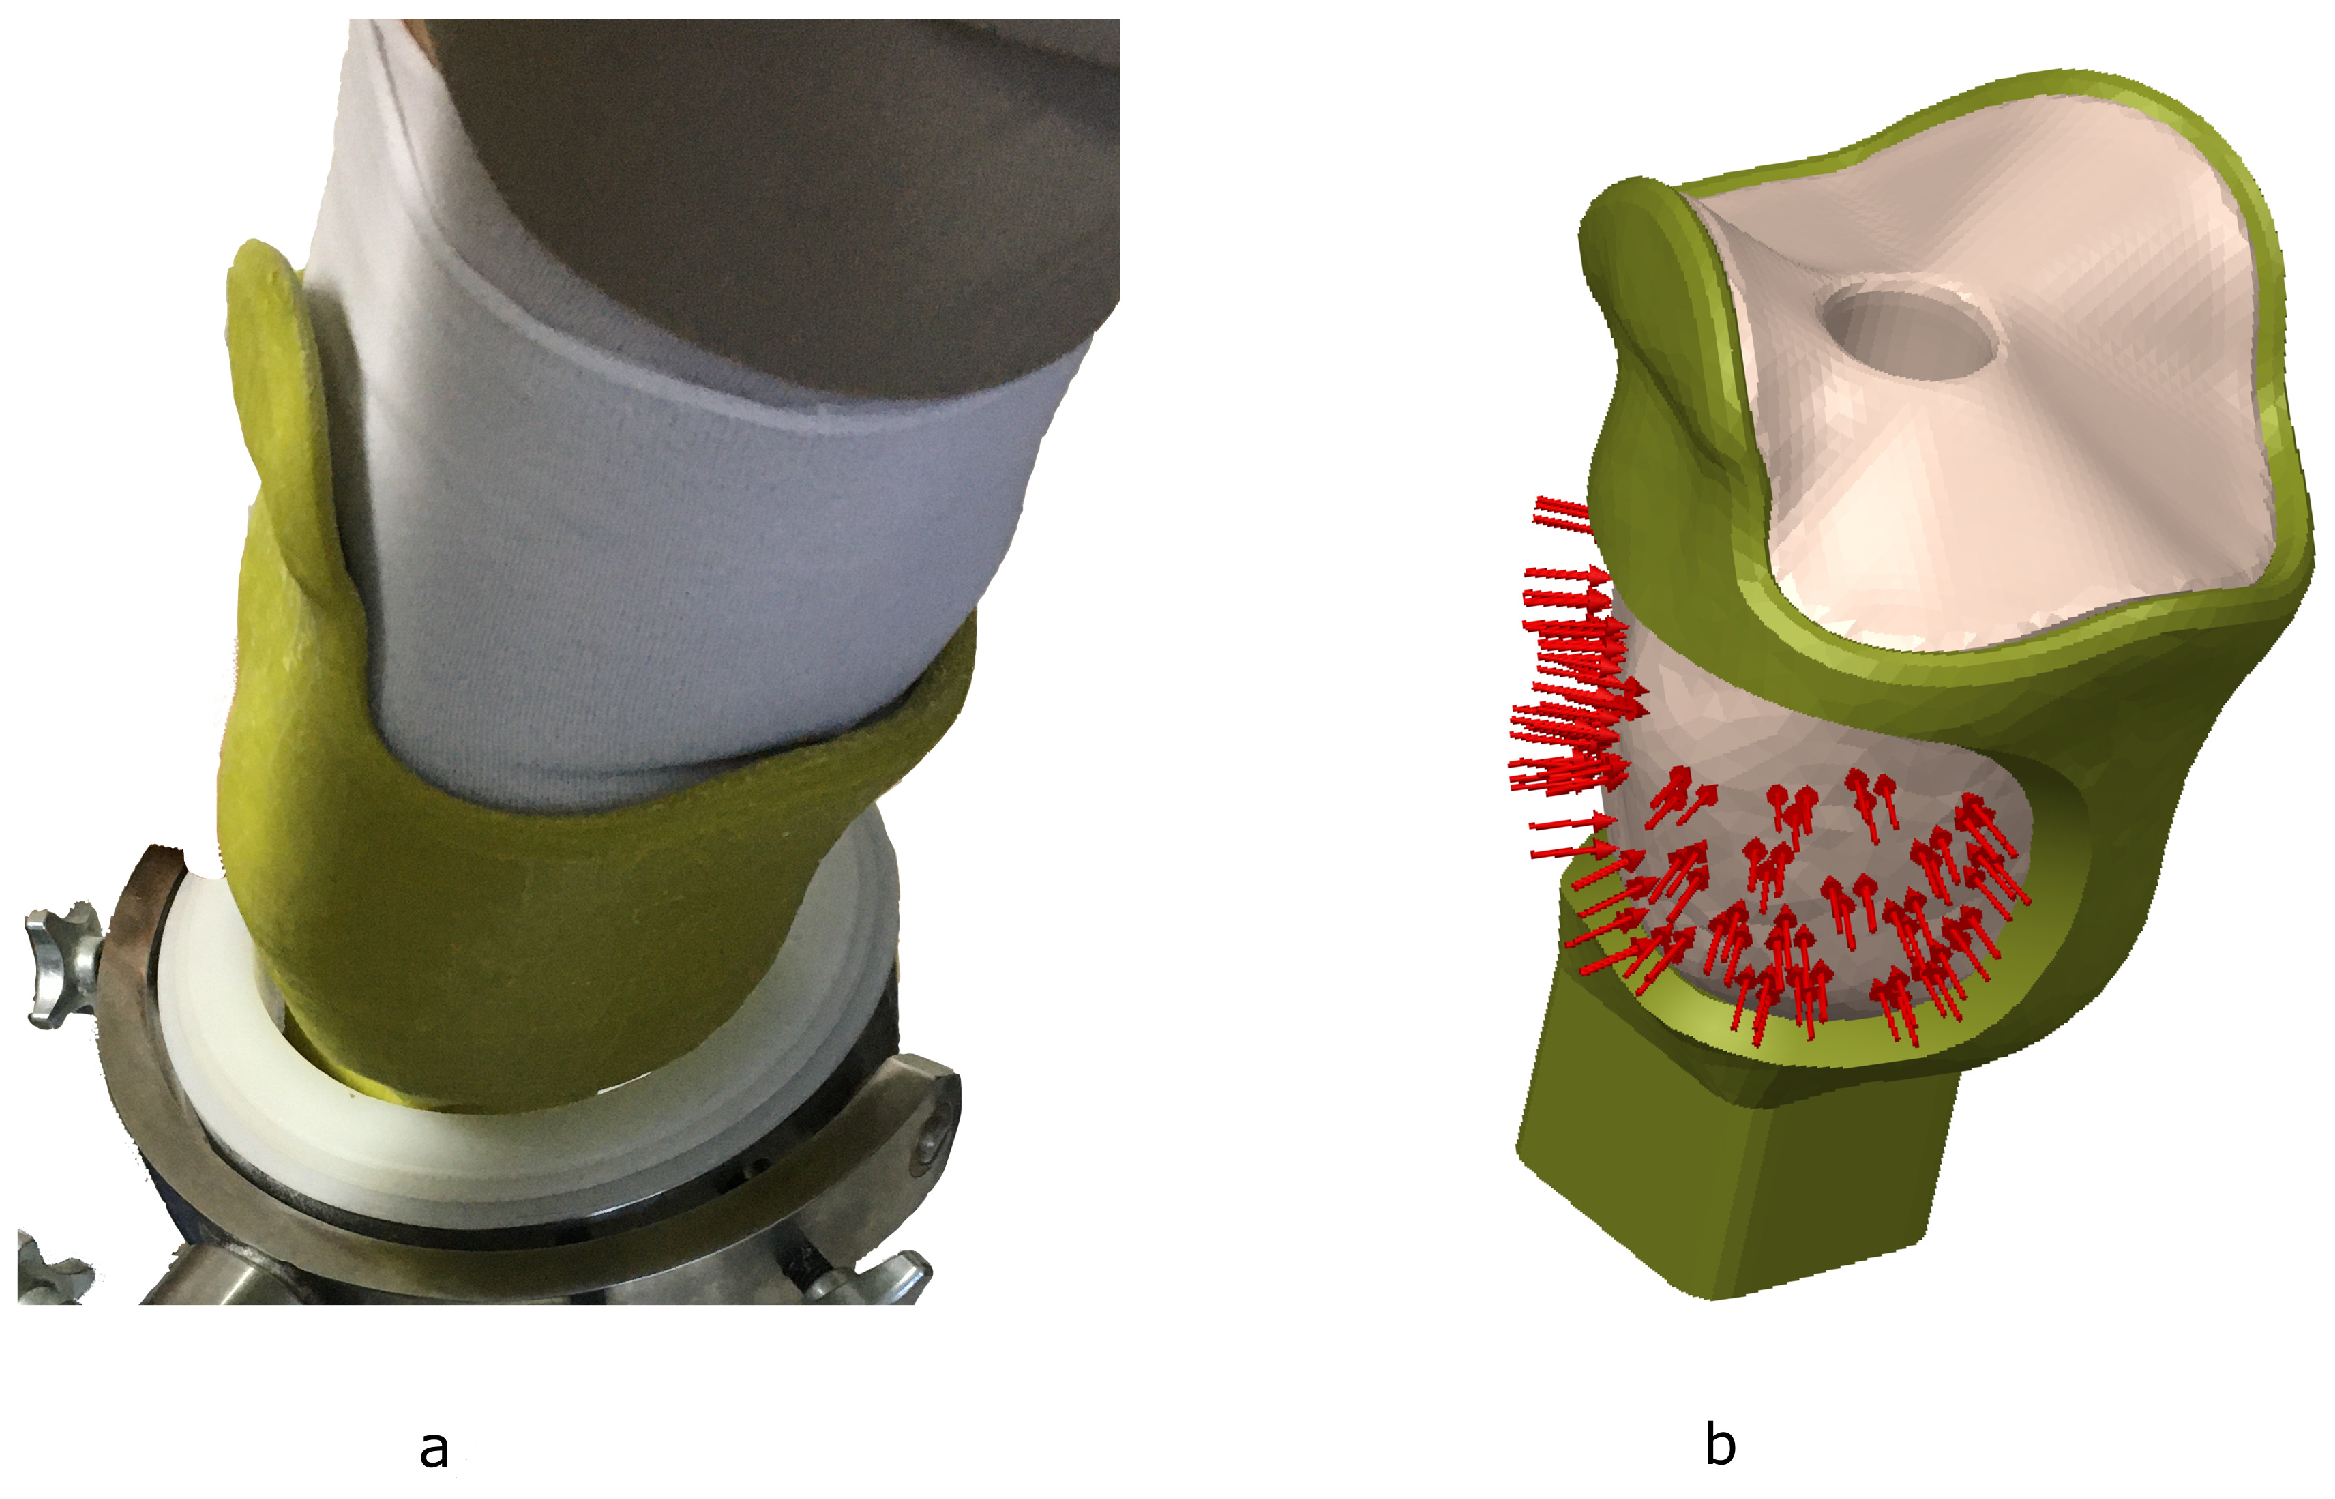

2. Materials and Methods

2.1. Materials and Equipment

2.3. Croi Location